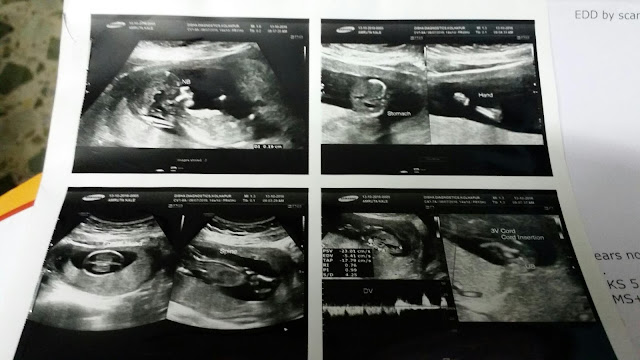

4 months completed

4 month completed to our baby 😙😙